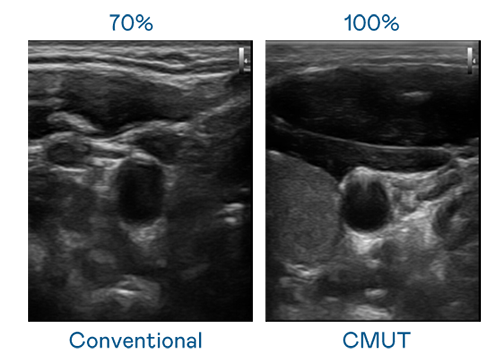

CMUT 技术是一种用电容式微机电元件来产生超音波讯号的技术。与传统 PZT 压电式技术相比,CMUT 频宽增加 30%,更宽频的超音波讯号让影像解析度大幅提升,是实现高影像品质医疗超音波扫描、促进精准医疗发展的关键技术。

超音波影像的解析度高低,首先取决于探头能发出的讯号频宽。优游ub8国际 CMUT 可提供高清晰的超音波讯号,提供高频宽、高灵敏度、影像纹理细节更高的超音波影像,协助医护人员缩短影像判读时间及利用精准的医疗影像进行诊断。